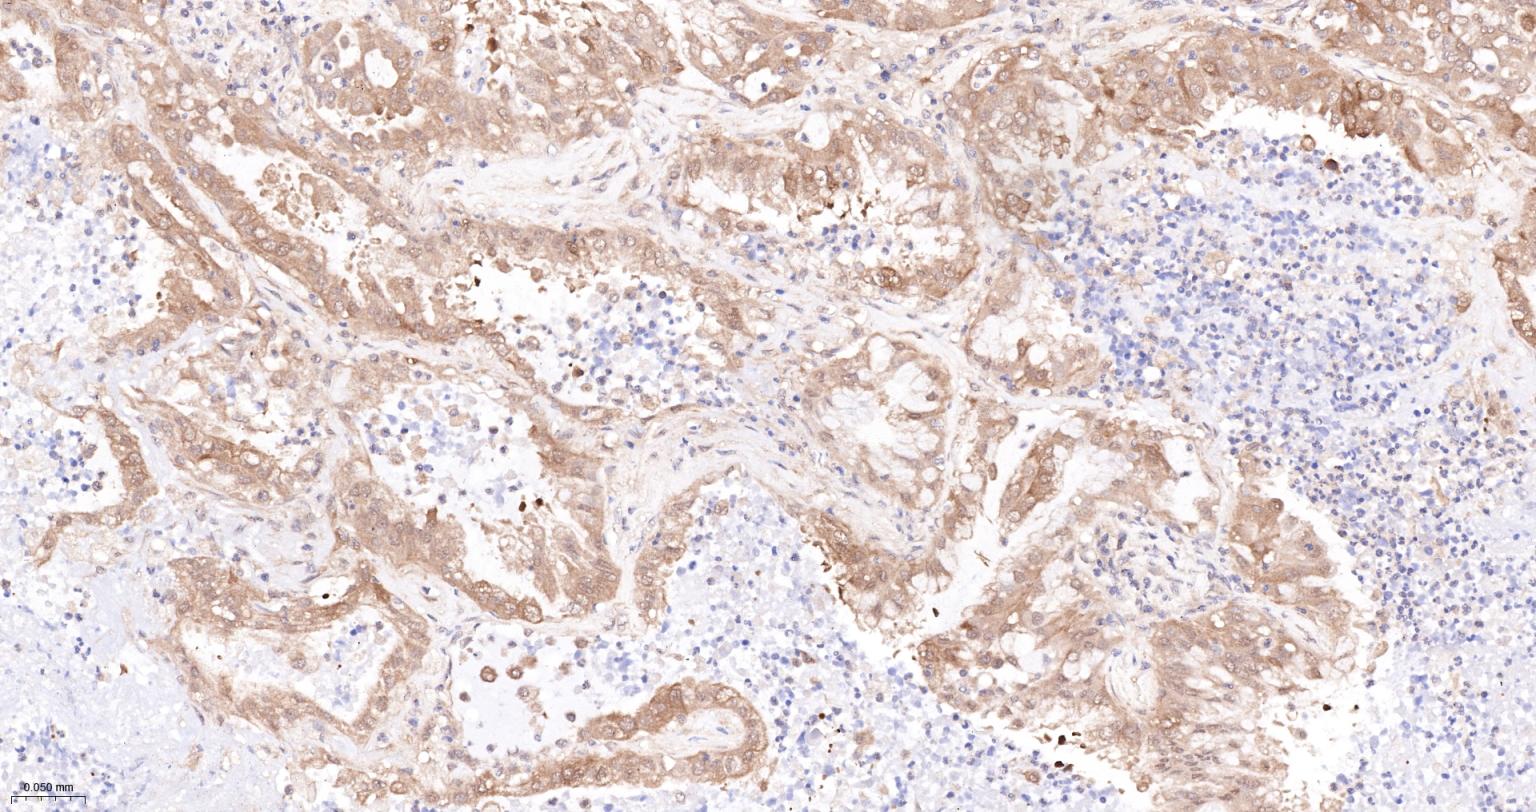

Paraformaldehyde-fixed, paraffin embedded Human Colon carcinoma; Antigen retrieval by boiling in sodium citrate buffer (pH6.0) for 15 min; The section was incubated with TFRC Monoclonal Antibody, Unconjugated (bsm-54633R) at 1:200 overnight at 4°C, followed by conjugation to the bs-0295G-HRP and DAB (C-0010) staining.